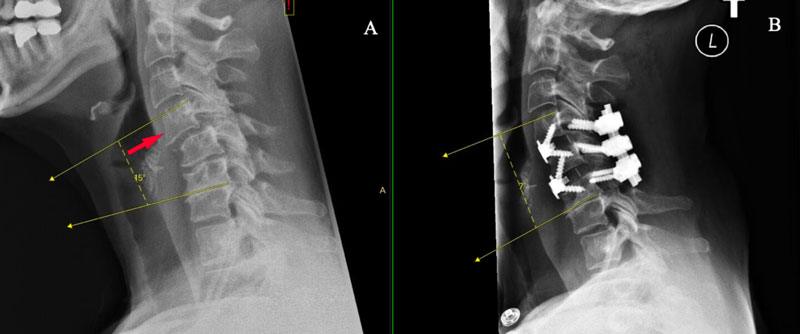

زمانی که پوزیشن یک مهره نسبت به دیگر مهرهها از راستای طبیعی خارج شود اصطلاحاً لیزخوردگی مهره یا اسپوندیلولیستزیس رخ میدهد که باعث بر هم خوردن قوس طبیعی و راستای طبیعی ستون فقرات میشود. بروز این عارضه میتواند بدلیل فشارهای مکرر وارد بر ستون فقرات گردنی مثل پایین انداختن طولانی مدت سر و گردن به سمت پایین، استفاده از بالشت با ارتفاع نامناسب، بلندکردن اجسام سنگین، انجام ورزشها و تمرینهای غیراصولی، وارد شدن ضربه به مهرههای گردنی، بیماریهای استخوانی و ضعف شدید عضلات گردن باشد. در بیمارانی که دچار این عارضه هستند علائمی مانند بی حسی، گزگز، درد در گردن و دستها احساس میشود و همچنین خشکی گردن و تغییرشکل انحنای طبیعی گردن ایجاد میشود.